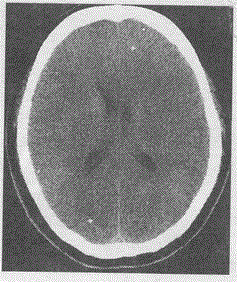

男,35岁,体检发现头颅CT如图,最可能的诊断是A.脑囊虫B.结核C.转移瘤D.灰质异位E.血管畸形

问题 男,35岁,体检发现头颅CT如图,最可能的诊断是

选项 A.脑囊虫 B.结核 C.转移瘤 D.灰质异位 E.血管畸形

答案 A